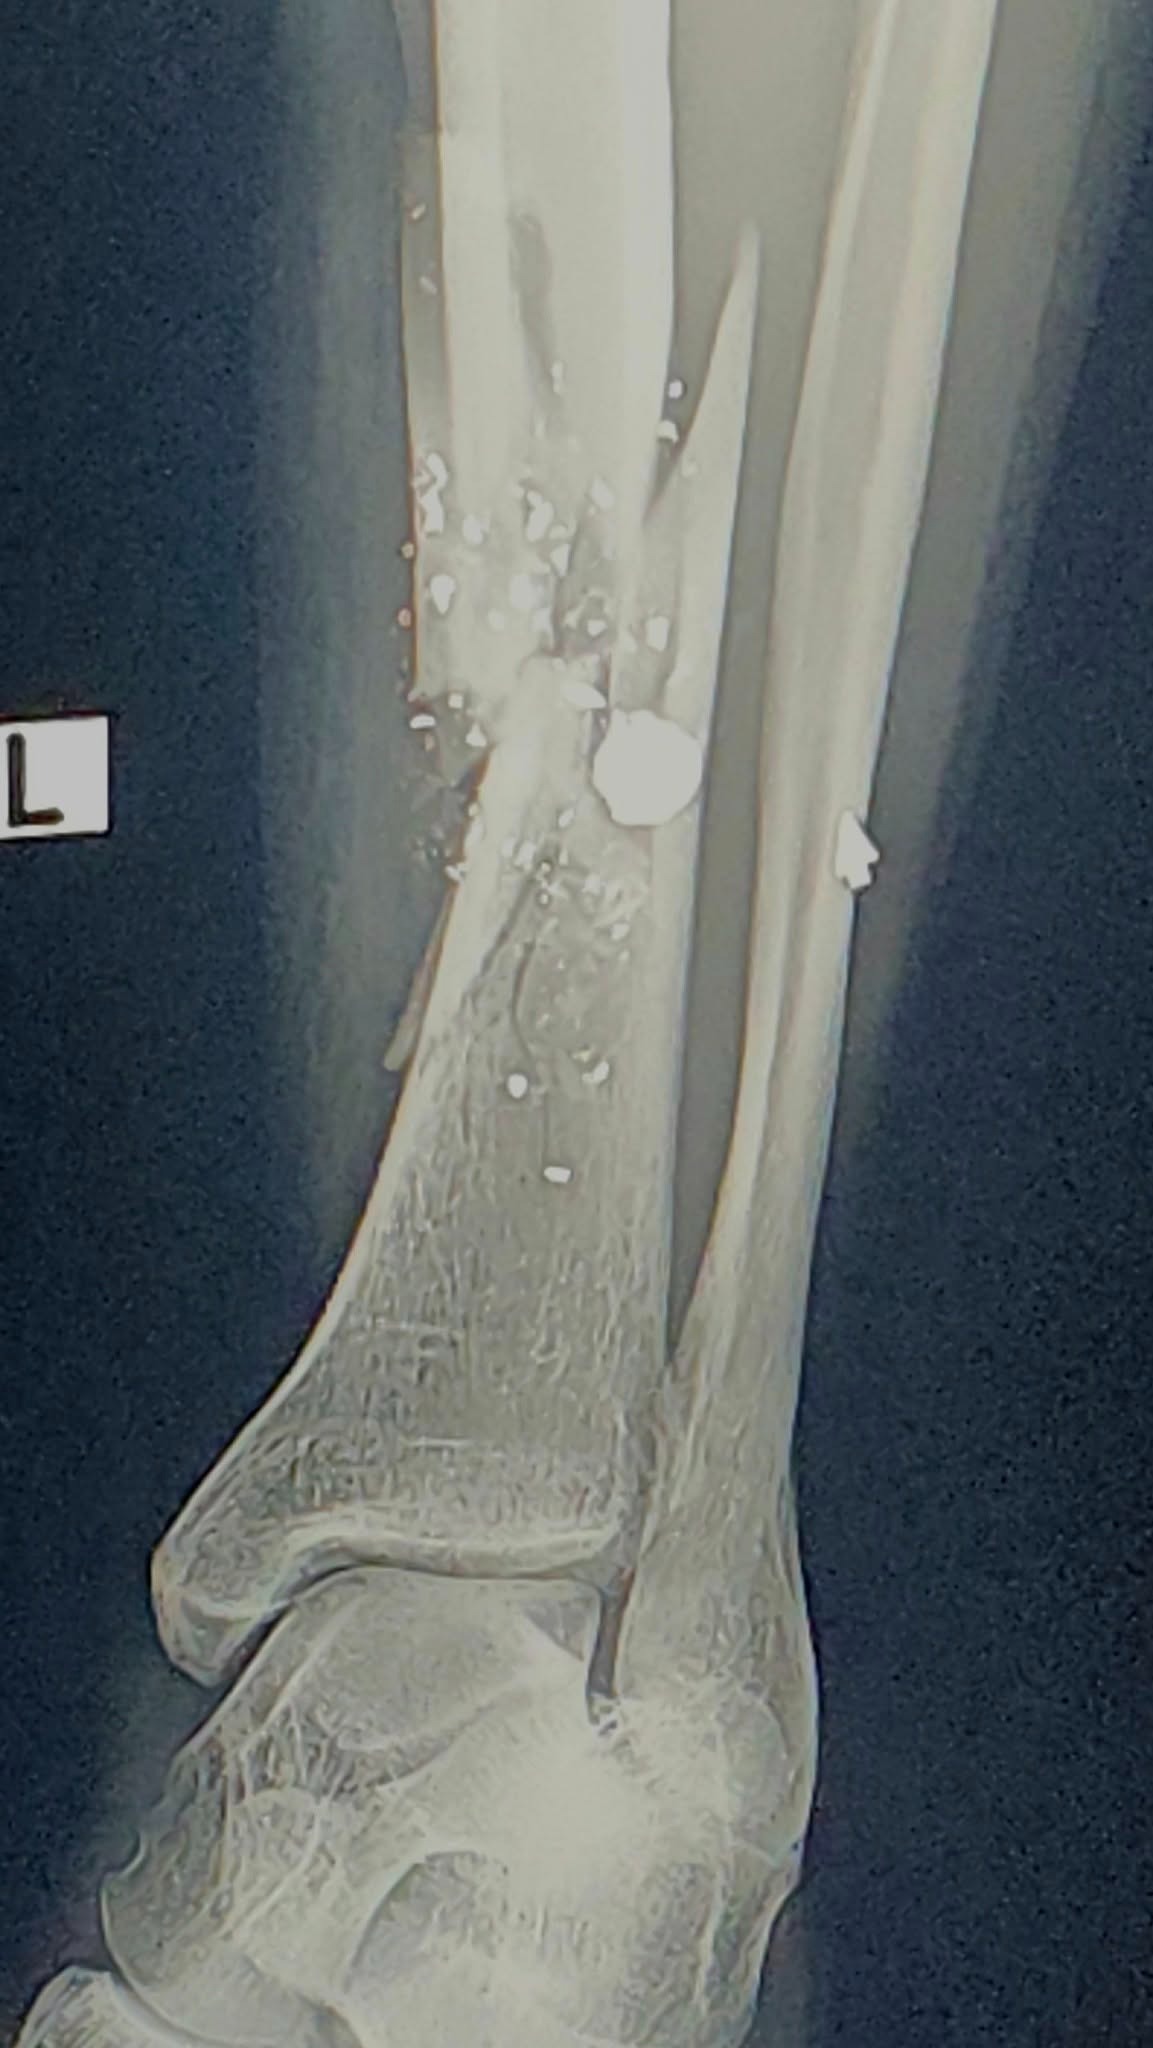

Jay saw an opportunity to flee when things started going south, and the guy opened fire into the street. One of the bullets hit him, shattering his leg.

Jay had surgery yesterday (7/30/25) and true to form, he’s taking it all in stride with humor and grace, though doctors say the bullet might have to stay in his leg permanently.